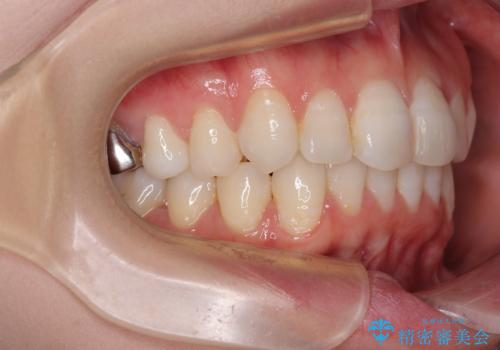

- 上下前歯のデコボコを改善したいとのことで来院された患者様です。

マウスピースを長時間装着し続ける自信はあまりないとのことでしたが、目立たない装置であれば頑張って装着するとのことで、インビザラインによる矯正治療を行うこととしました。

初めの1年くらいは何とか頑張って装着してくださいましたが、途中から変化をあまり感じられなくなり、日々の装着時間は徐々に短くなってしまいました。

前歯のデコボコはもっと改善できましたが、3年半が経過し、初診時と比べたら大幅に良くなったとのことで終了することとなりました。